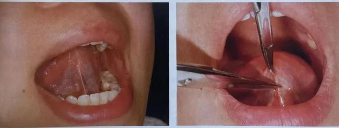

舌系带过短

舌系带过短是指胎儿娩出后舌系带未退缩到舌根下, 导致舌头不能伸出口外, 舌尖不能上翘,常表现为舌前伸时舌尖呈W型,舌上抬困难。患儿会出现舌活动异常、发声异常等情况。

系带成形术可以在局麻下进行,对于不能配合手术的幼儿患者,一般选择在吸入麻醉(患儿入睡)状态下手术。